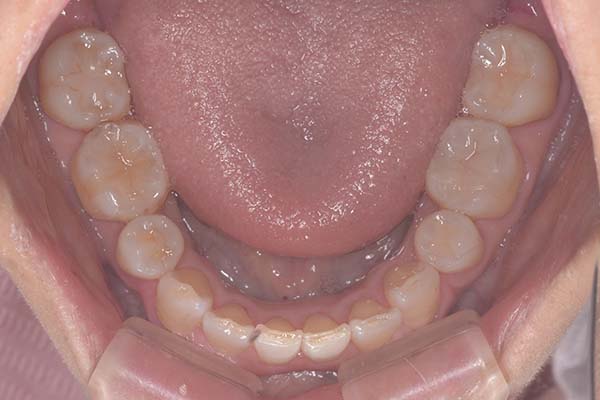

年齢・性別30歳 男性

主訴受け口と前歯の

反対咬合を治したい

治療期間14ヶ月

治療費用装置代880,000円(税込)

治療内容ワイヤー矯正

治療のリスク後戻りの可能性